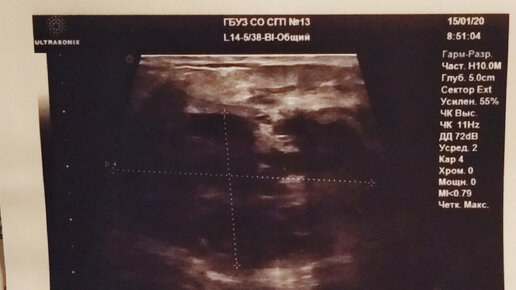

Это продолжение моей истории как я боролась с застоем в груди. Если интересно почитать с чего все начиналось, то вот первая и вторая часть. В прошлой статье я остановилась на том, что ко мне приходила еще раз консультант по ГВ и она меня еще раз расцедила. Вы не поверите как я радовалась, тому что все моя шишка в груди исчезла и застоя больше нет. Я продолжала сцеживаться. Вы спросите зачем? Молока при сцеживание набиралось мало, не всегда одинаковое количество. И как мне казалась, что его мало и ребенку не хватает...

Лично я за 1,5 года (еще кормлю) кормления грудью ни раз ощущала это не приятное явление. Обычно начинается с боли в груди,после появляется уплотнение ,далее возможна повышенная температура тела...